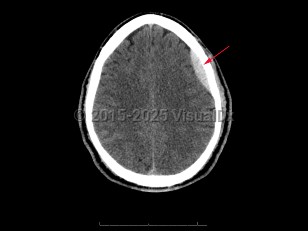

Epidural intracranial hematoma

The classic presentation involves a brief post-traumatic loss of consciousness, then several minutes to hours of a lucid interval, followed by obtundation and focal neurologic deficits. While this classic clinical description is widely taught, it is seen in < 20% of cases. Other less specific signs and symptoms include headache, nausea and emesis, seizures, neurologic deficits (contralateral weakness, hyperreflexia), papilledema, pupil-involving third-nerve palsy, somnolence, or coma.